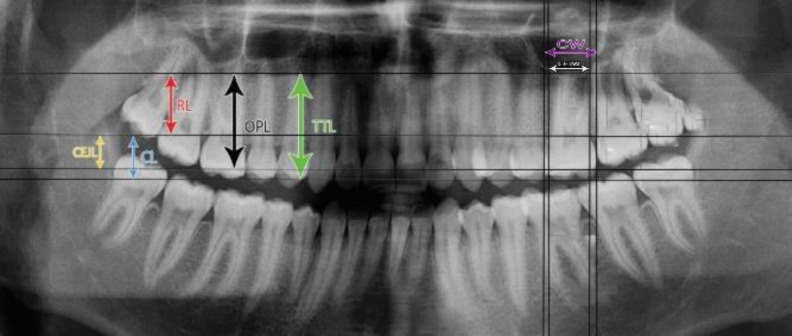

Objectives: This study assessed sex estimation of Iranians according to maxillary left first molar measurements made on panoramic radiographs using classical and machine-learning classifiers. Materials and Methods: In this cross-sectional study, tooth length- and width-related variables were calculated for maxillary left first molars on 131 panoramic radiographs (65 males, 66 females; age range of 18-30 years). A subsample of the radiographs was selected and reevaluated by two examiners after 1 month. The intra-class correlation coefficient (ICC) was calculated to assess reliability. The regularized discriminant analysis (RDA), support vector machine (SVM), and cascade-forward and feed-forward neural network models were used for sex estimation. Comparisons were made with the Mann-Whitney and t tests. Results: The intra-observer reliability was 0.9. SVM had the best performance on the test data in both classification schemes. The crown length at the cementoenamel junction (CEJL) and total crown length (CL) in the classification scheme I (sex estimation based on length and width variables), and CEJL/root length (RL), cementoenamel junction width (CEJW)/CEJL, and RL/total tooth length (TTL) in the classification scheme II (sex estimation based on the ratio of variables) were important variables for sex estimation determined by the SVM model. The CEJL had the highest discriminative potential with an area under the curve (AUC) of 78.8. The ratio of variables did not substantially improve sex estimation compared with single variables. Conclusion: CEJL is a reliable measure for sex estimation in Iranians with values higher than 6.25 indicating the male sex and other values indicating the female sex.